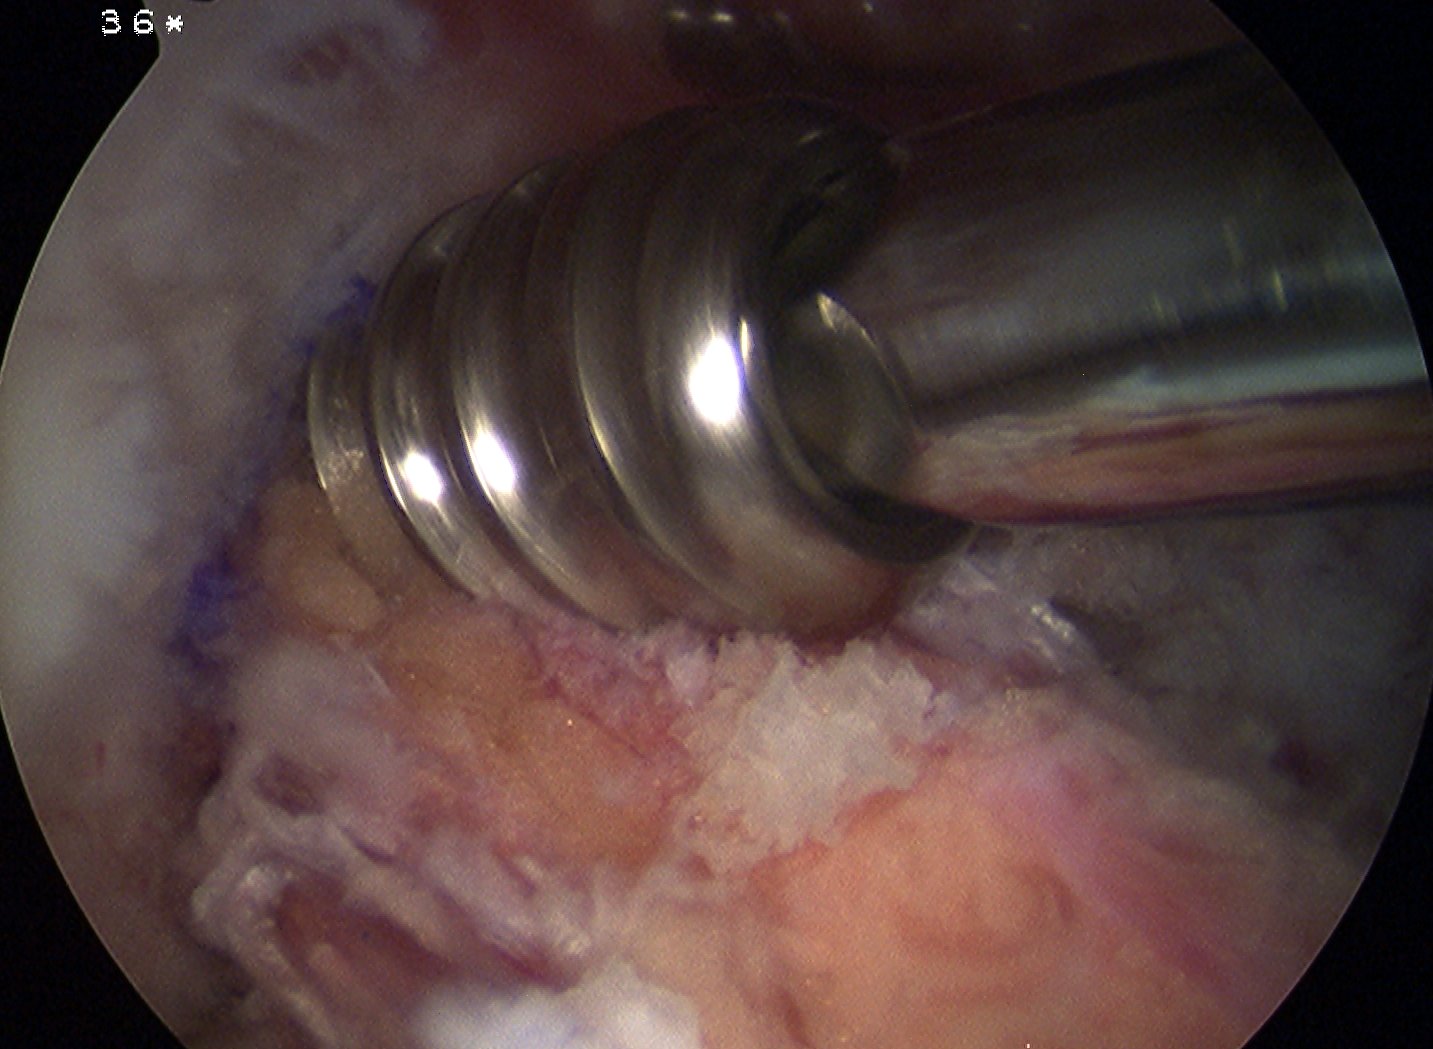

Screw Fixation

Femoral screw

- need to be careful ans can blowout back wall or create divergent screw

- hyperflex knee +++

- this step is very important to prevent divergent screw

- expose femoral tunnel with good vision

- pass screw guide wire anterior to bone graft so as not to blow out tunnel

- insert 7 x 25 mm screw ensuring that the screw threads engage the tunnel